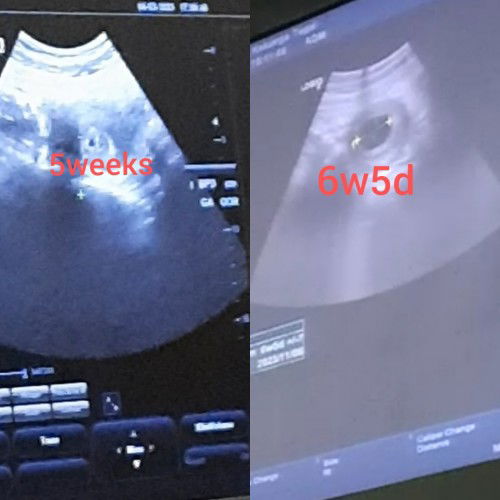

HAMIL 6W5D BELUM TERLIHAT JANIN

Moms, tadi sore saya usg ke dokter krn tiba2 flek darah segar tp tdk ada gumpalan. Setelah di cek usia 6w5d pdhl kalau sesuai hpht harusnya 7weeks dan ternyata belum keliatan janinnya dgn uk kantong 2,47cm. Apa itu normal moms? Atau tanda2 hamil BO? Takut bgt krn ini kehamilan pertama😭#seriusnanya #firstmom #pleasehelp